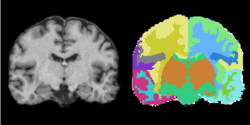

Pediatric MS Study

- Collaborator: Tanuja Chitnis PI (Brigham and Women's Hospital/Multiple Sclerosis Center), Alexander Zaitsev (Brigham and Women's Hospital/Surgical Planning Laboratory) and Massachusetts General Hospital

- Short description: Evaluate brain atrophy for pediatric MS Patients

- Image specification: 3 Tesla, Scanner: SIGNA HDx / GE MEDICAL SYSTEMS, 3D MPRAGE, Sagital Scans, TR/TI/TE=24/0/7 ms, pixel_xsize = 0.976600, pixel_ysize = 0.976600, fov = 250.009598, aspect = 1.535941, thick = 1.500000, space = 0.000000

- Used Task: MRI Human Brain